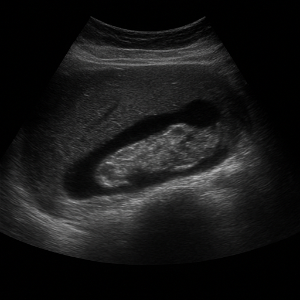

신장은 결석, 수신증(소변이 막혀 고여서 생긴 변화), 낭종, 종양 등의 상태를 초음파로 볼 수 있어요. 부신은 위치가 작고 깊지만, 우연종 같은 병변이 의심될 때 관찰할 수 있답니다.

신장 결석, 신부전, 낭종

- 신장 결석

콩팥에 생긴 작은 돌들은 초음파에서 반짝이며 그림자를 동반해 쉽게 보일 수 있어요. - 신부전 (수신증 등)

소변이 막혀서 신장이 붓는 상태를 ‘수신증’이라고 하는데요, 초음파로 신장의 부종이나 이상을 확인할 수 있어요. - 신장 낭종이나 종양

주머니처럼 생긴 낭종이나 덩어리가 있으면 초음파로 확인 가능해요.